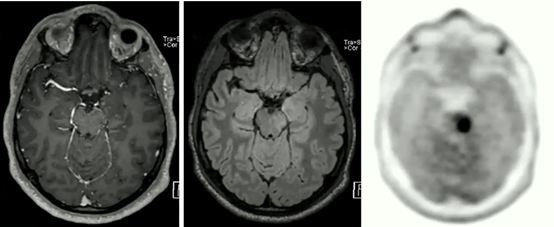

此外,神經腫瘤學家使用PET/MRI監測正在接受治療的患者,主要是識別手術切除后可能復發的膠質母細胞瘤。Umutlu展示了這樣一個例子,在這種情況下,單獨的MRI可能會漏掉腫瘤,但這在添加PET后清楚地顯示出來。

PET/MRI的PET成分可以顯示僅通過MRI可能無法檢測到的腦腫瘤。

她說:“這是PET成分真正幫助我們在腦瘤的第二種表現形式方面做出明確診斷的案例之一。”